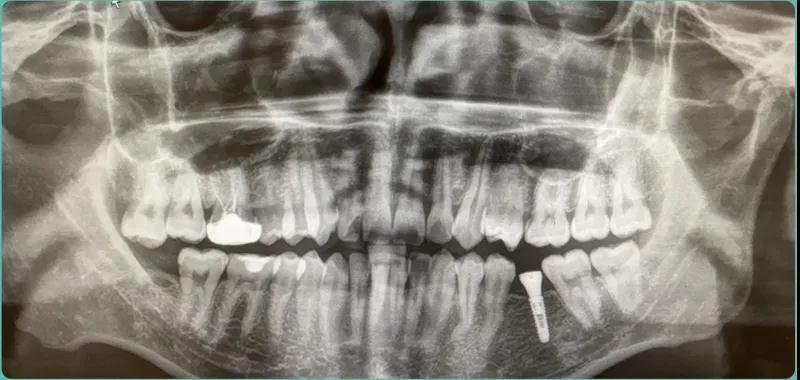

种植嘉宾术前资料介绍,年龄27岁,种植左下颌6号牙。

姚江武院长为患者进行种牙直播,种一颗牙仅需要5分钟就完成了,种牙顾客来到现场,分享种牙感受。